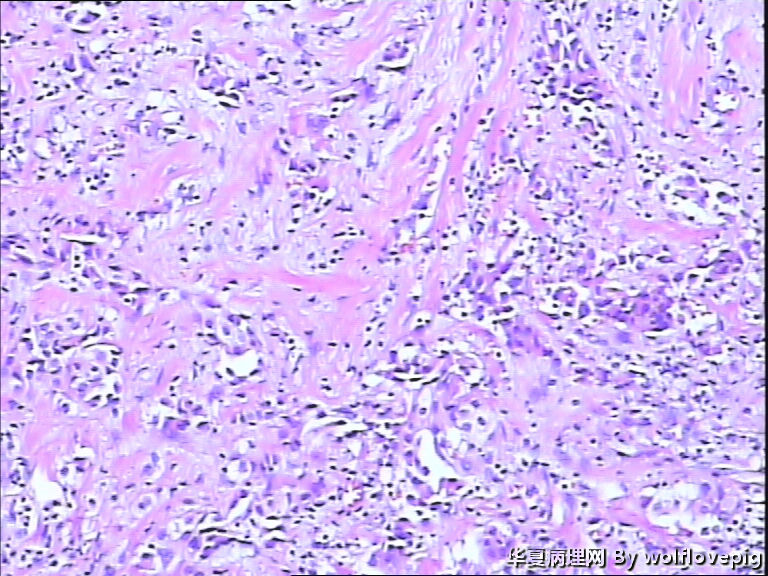

女,60y,发现右乳包块6+月。

灰白不整形组织一块:3*2*1.5cm,切面有一灰白区域,边界欠清,质韧。

标签:乳腺浸润性癌

浸润性癌。

浸润性导管癌,最好标记肌上皮。

浸润性导管癌

浸润性导管癌,分化差,除外混合癌(导管癌+小叶癌),免疫组化证实。(本例图像很多,局部炎症反应重,瘤细胞还成合体样无腺管形成似髓样癌,局部似炎性乳癌,局部似小叶癌,呵呵)